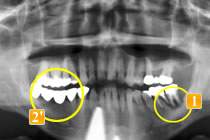

56歳男性

インプラント治療の必要性を自覚して他の歯科医院より依頼されたケースです。

初診時、左下一番奥の歯(レントゲンでは右下

)は骨が吸収してしまっています。

この状態で手前の歯と連結して長期間経過したため、より骨が無くなってしまいました。

骨が少なすぎてインプラントを打つ厚みがありません。この時点では手術はできませんと説明しました。

この歯を抜歯した際に骨移植を行いました。あまりに骨が少なかったのでインプラントを打てる厚みまで回復するのに2年の経過観察をしました。

先に右で噛めるようにインプラントにて治療を行い、

骨移植し骨ができたところでインプラント植立を行いました。右下奥のブリッジ(レントゲンでは

)は、ブリッジが長かったためか、親知らずが溶けてしまっています。負担の大きい手前の2本の小臼歯も揺れていました。

手術した結果、インプラントで噛むことができて、手前の歯の骨が安定しました。

このように、インプラントは他の歯を長持ちさせる為にも有効な方法です。